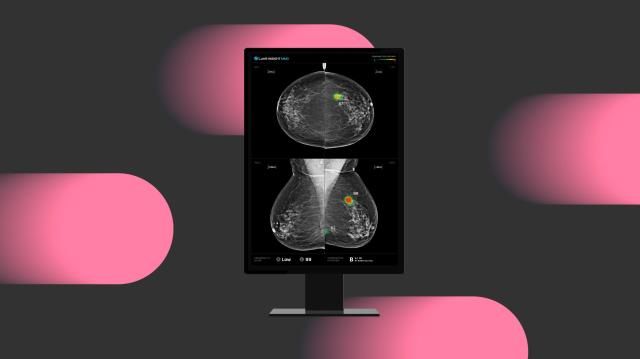

[사진=루닛]

의료 인공지능(AI) 기업 루닛의 유방촬영술 AI 영상분석 솔루션 ‘루닛 인사이트 MMG’를 활용하면 유방암 발견율이 늘어난다는 사실이 입증됐다.

루닛은 인사이트 MMG에 대한 대규모 다기관 전향적 연구 결과가 국제 학술지 ‘네이처 커뮤니케이션즈’에 게재됐다고 10일 밝혔다.